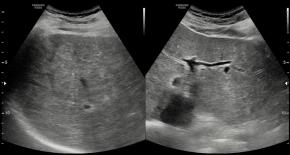

Comments Although the hepatic parenchyma may initially appear coarse, the liver actually shows numerous tiny hyperechoic foci with comet-tail artifacts scattered throughout the parenchyma. In addition, there are no accompanying findings suggestive of chronic liver disease or cirrhosis, such as liver contour blunting, surface nodularity, liver volume redistribution, dilatation of the portal vein, or splenomegaly.

• Multiple tiny low-attenuating lesions are scattered throughout the hepatic parenchyma, which is a characteristic CT finding of biliary hamartomatosis.